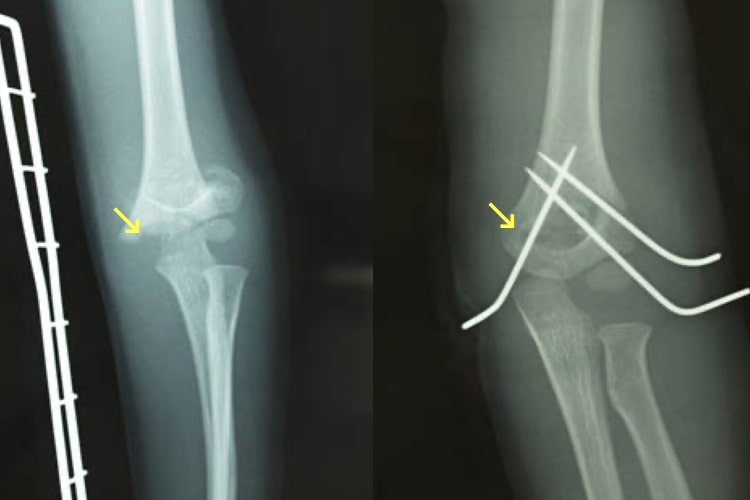

手術1件。当直 : ただの医師じゃねえかこんなもん。

手術2件 : ただの医師じゃねえかこんなもん。